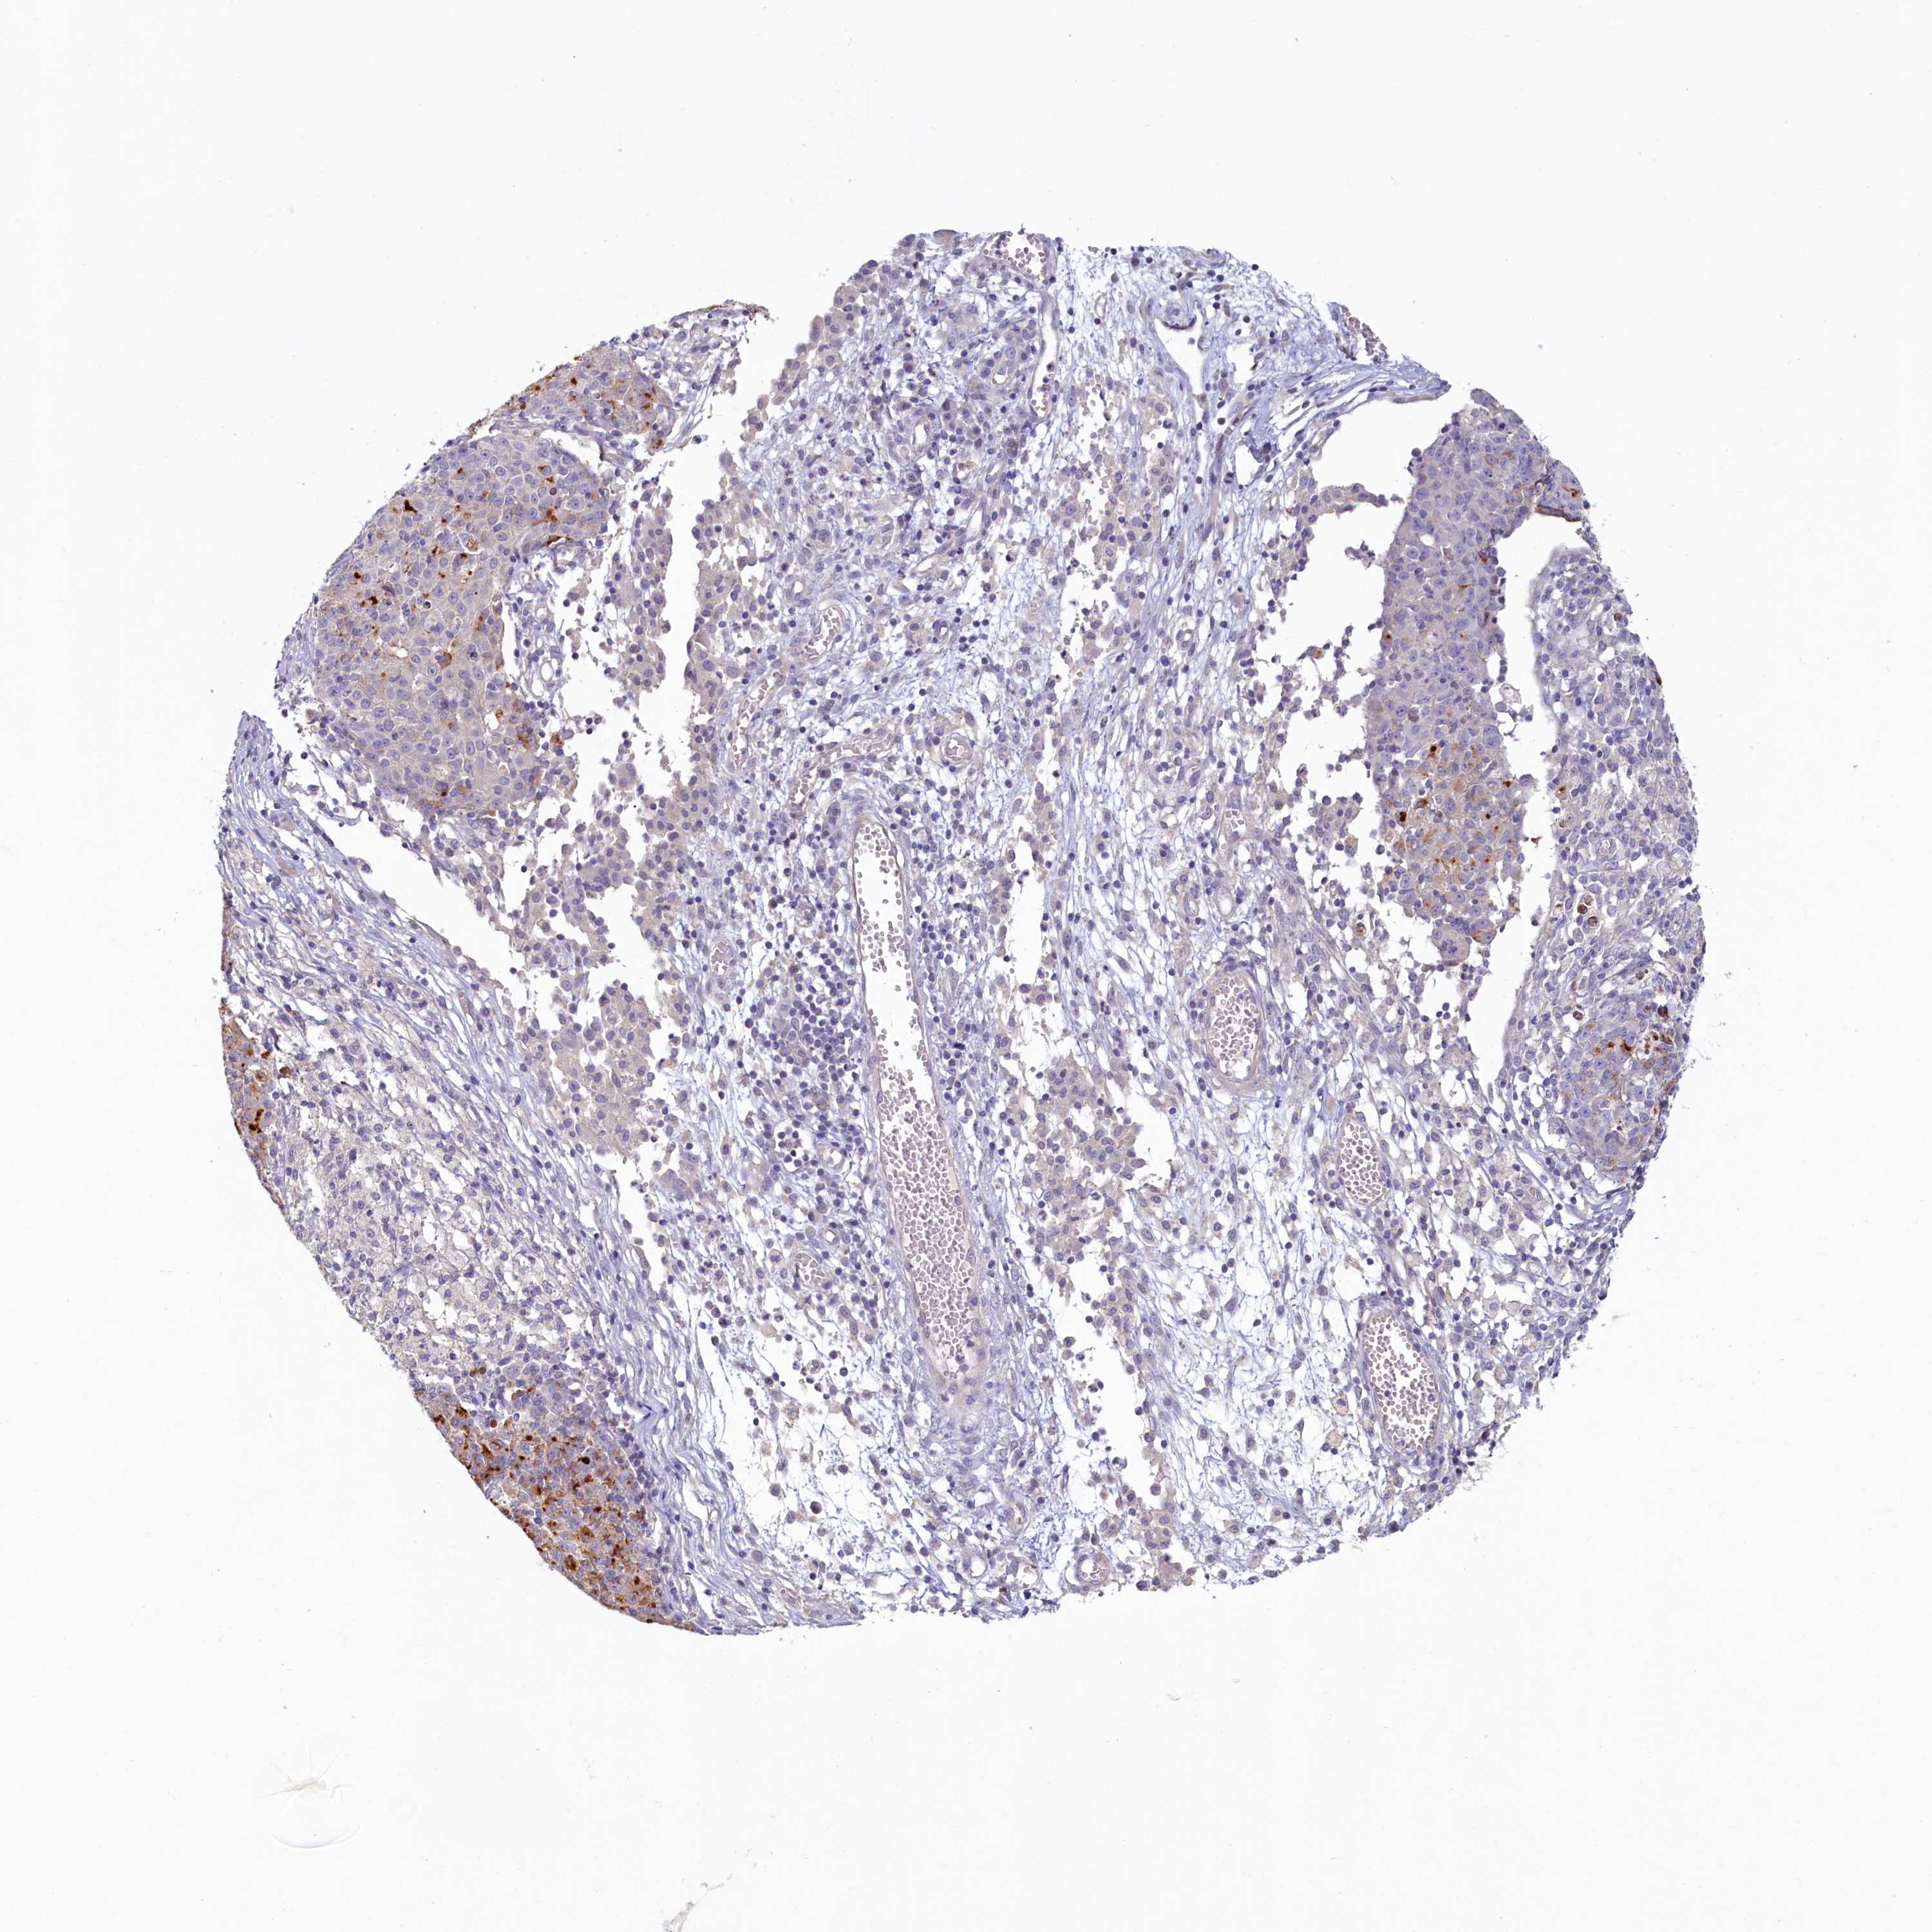

OVARIAN CANCER - Protein expressioni

A mouse-over function shows sample information and annotation data. Click on an image to view it in a full screen mode. Samples can be filtered based on level of antibody staining by selecting one or several of the following categories: high, medium, low and not detected. The assay and annotation is described here.

Note that samples used for immunohistochemistry by the Human Protein Atlas do not correspond to samples in the TCGA dataset.

Antibody stainingi

Antibody staining in the annotated cell types in the current human tissue is reported as not detected, low, medium, or high, based on conventional immunohistochemistry profiling in selected tissues. This score is based on the combination of the staining intensity and fraction of stained cells.

Each image is clickable and will lead to virtual microscopy that enables deeper exploration of all samples and also displays staining intensity scores, fraction scores and subcellular localization as well as patient and tissue information for each sample.

Antibody HPA037434

Cystadenocarcinoma, serous, NOS

Carcinoma, endometroid

Cystadenocarcinoma, mucinous, NOS

Carcinoma, NOS